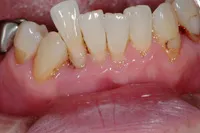

インプラントでの臼歯のかみ合わせの不調和改善例

■治療前

全ての歯の高さが、波を打ったような状態になって、咬み合わせが難しくなっています。

■治療後

術前にあった、歯の高さの不調和の問題が改善できています。

| 主訴 | かみ合わせが悪くかみにくい・時々顎関節症による痛みがある |

|---|---|

| 治療方法 | 補綴治療(波打ったような歯の高さを平面になるように揃えてかみやすくした) |

| 治療期間 | 約1年 |

| 通院回数等 | 約20回 |

| 費用 | 約400万円 |

| リスク・副作用 | 補綴物が過度な力で破損するリスクがある |